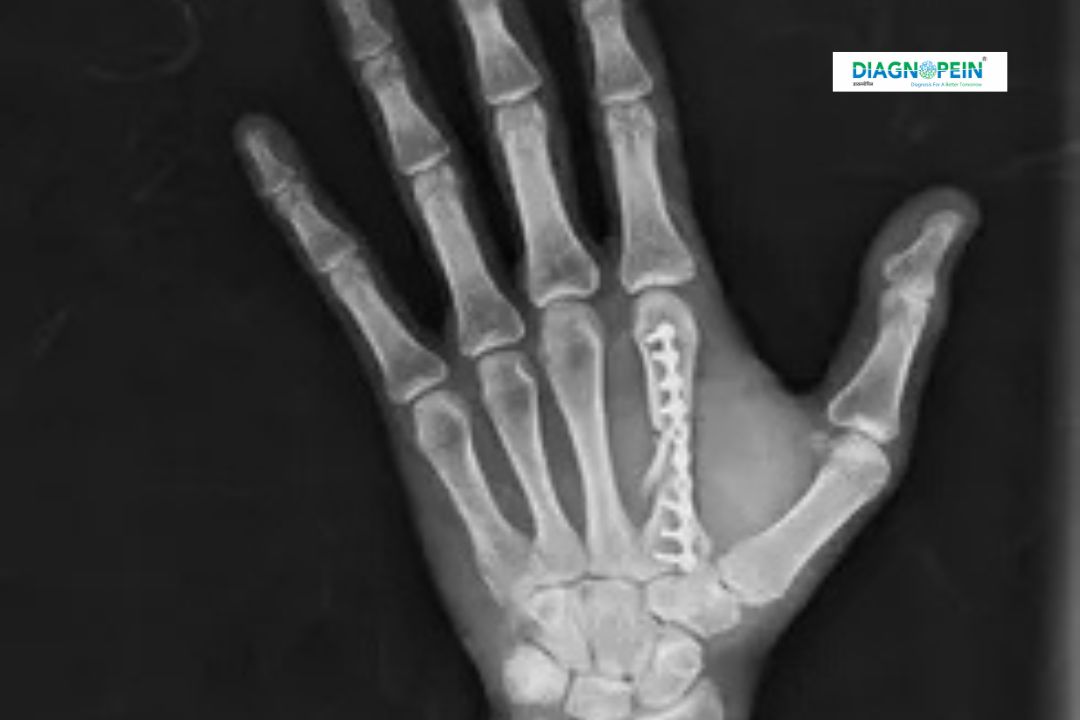

X-RAY RT. HAND AP (Anteroposterior View) is a commonly performed radiological imaging test used to examine the bones and joints of the right hand. This diagnostic X-ray provides a clear frontal view of the hand, including fingers, metacarpals, and wrist alignment. At Diagnopein, X-RAY RT. HAND AP in Nashik is conducted using advanced digital X-ray equipment to ensure accurate and fast diagnosis.

In cases of chronic conditions like arthritis, osteoporosis, or rheumatoid arthritis, X-RAY RT. HAND AP in Nashik helps monitor disease progression and treatment response. It is also useful for pre-surgical planning and post-surgical follow-up, making it a crucial diagnostic tool in orthopedic care.

The radiology technician positions the X-ray machine above the hand and captures the image in the anteroposterior view. The entire X-RAY RT. HAND AP test in Nashik takes only a few minutes. Patients are advised to remove rings, bangles, or metal objects before the scan for accurate results.